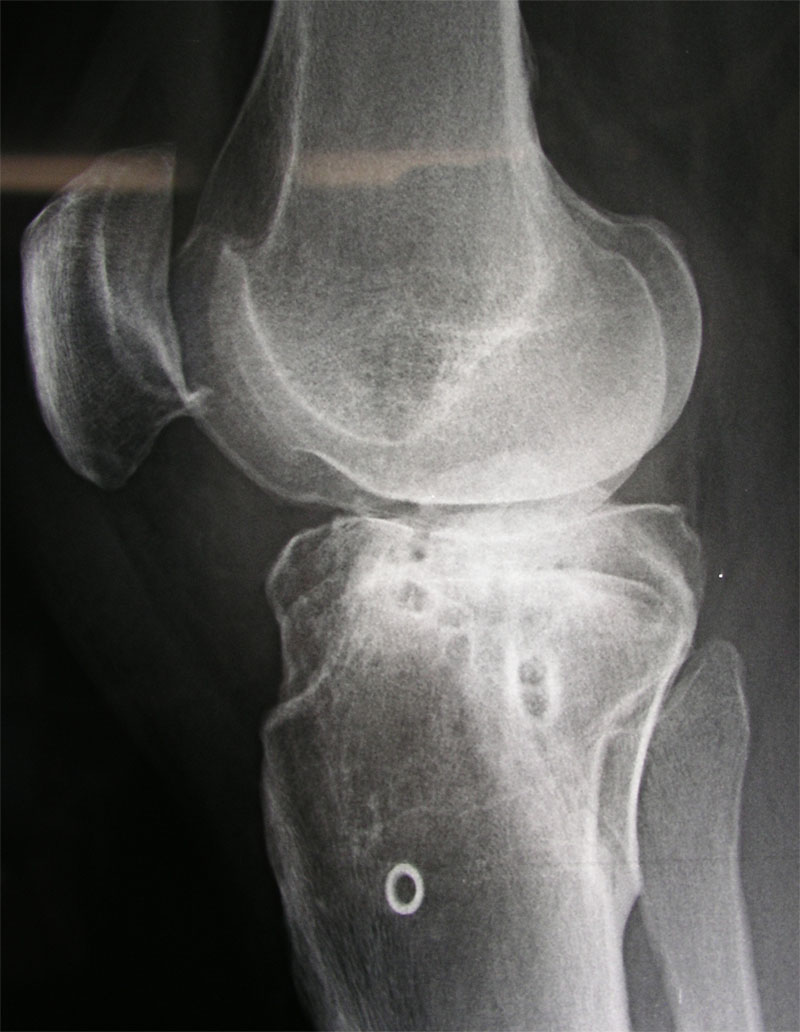

In diesem Röntgenbild (für einmal von der anderen Seite aufgenommen) von Anfang Dezember 2002 (Inselspital Bern, anlässlich der Punktion - aufs Bild klicken für grössere Fassung) sieht man wiederum schön den mutmasslichen Osteophyten an der Patella, den ich immer mehr für die Schmerzen verantwortlich mache, die nunmehr seit einem halben Jahr andauern.

Hier ist eine Ausschnittsvergrösserung der unteren Patellareagion zu sehen (im Bild oben eingerahmt).